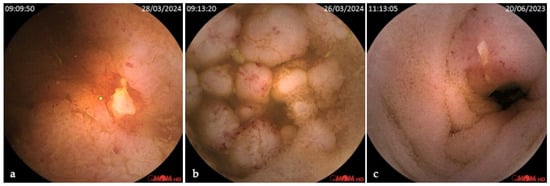

Background/Objectives: Robotic capsule endoscopy (RCE) is an emerging technology that combines magnetically controlled gastric navigation with conventional capsule enteroscopy (CE), enabling a minimally invasive, comprehensive evaluation of the upper- and mid-gastrointestinal tract. This study aimed to characterize the real-world implementation and diagnostic [...] Read more.

Background/Objectives: Robotic capsule endoscopy (RCE) is an emerging technology that combines magnetically controlled gastric navigation with conventional capsule enteroscopy (CE), enabling a minimally invasive, comprehensive evaluation of the upper- and mid-gastrointestinal tract. This study aimed to characterize the real-world implementation and diagnostic performance of RCE in a European tertiary referral center. Methods: A retrospective, single-center analysis was conducted on adult patients (≥18 years) who underwent RCE (Omom RC) between June 2023 and July 2025. Eligible patients had a clinical indication for small bowel CE and a concurrent requirement for diagnostic gastroscopy or reassessment of known gastric lesions. The RCE protocol comprised an initial robotic-guided gastric examination followed by passive transit through the small bowel. Results: A total of 85 patients were included (52% female), with a median age of 49 years (IQR 40–64). The most common indications were suspected or established inflammatory bowel disease (57%) and iron deficiency anemia (31%). Gastric preparation was rated at least fair in 98% of cases, with good preparation in 38%. Median gastric transit time was 74 min (IQR 35–106). Relevant gastric findings were identified in 39 cases (46%), namely polyps (18%) and angiectasias (8%, including one with active bleeding), in addition to signs of chronic gastritis. Thirteen patients underwent subsequent endoscopy, resulting in seven therapeutic procedures. Small bowel findings were present in 60 patients (71%), including P3 (active bleeding) in 3% and P2 lesions (angiectasias, ulcers, tumors, varices) in 39%. One moderate adverse event occurred: small bowel capsule retention in a patient with multifocal neuroendocrine tumor and ileostomy, requiring endoscopic intervention. Conclusions: Robotic capsule endoscopy is a feasible tool for dual-region gastrointestinal evaluation. It enables high-quality gastric visualization, facilitates early detection of clinically actionable lesions, and maintains the diagnostic yield expected from standard small bowel CE. These findings support the integration of RCE into diagnostic pathways for patients requiring simultaneous gastric and small bowel assessment. Full article

Show Figures

Figure 1